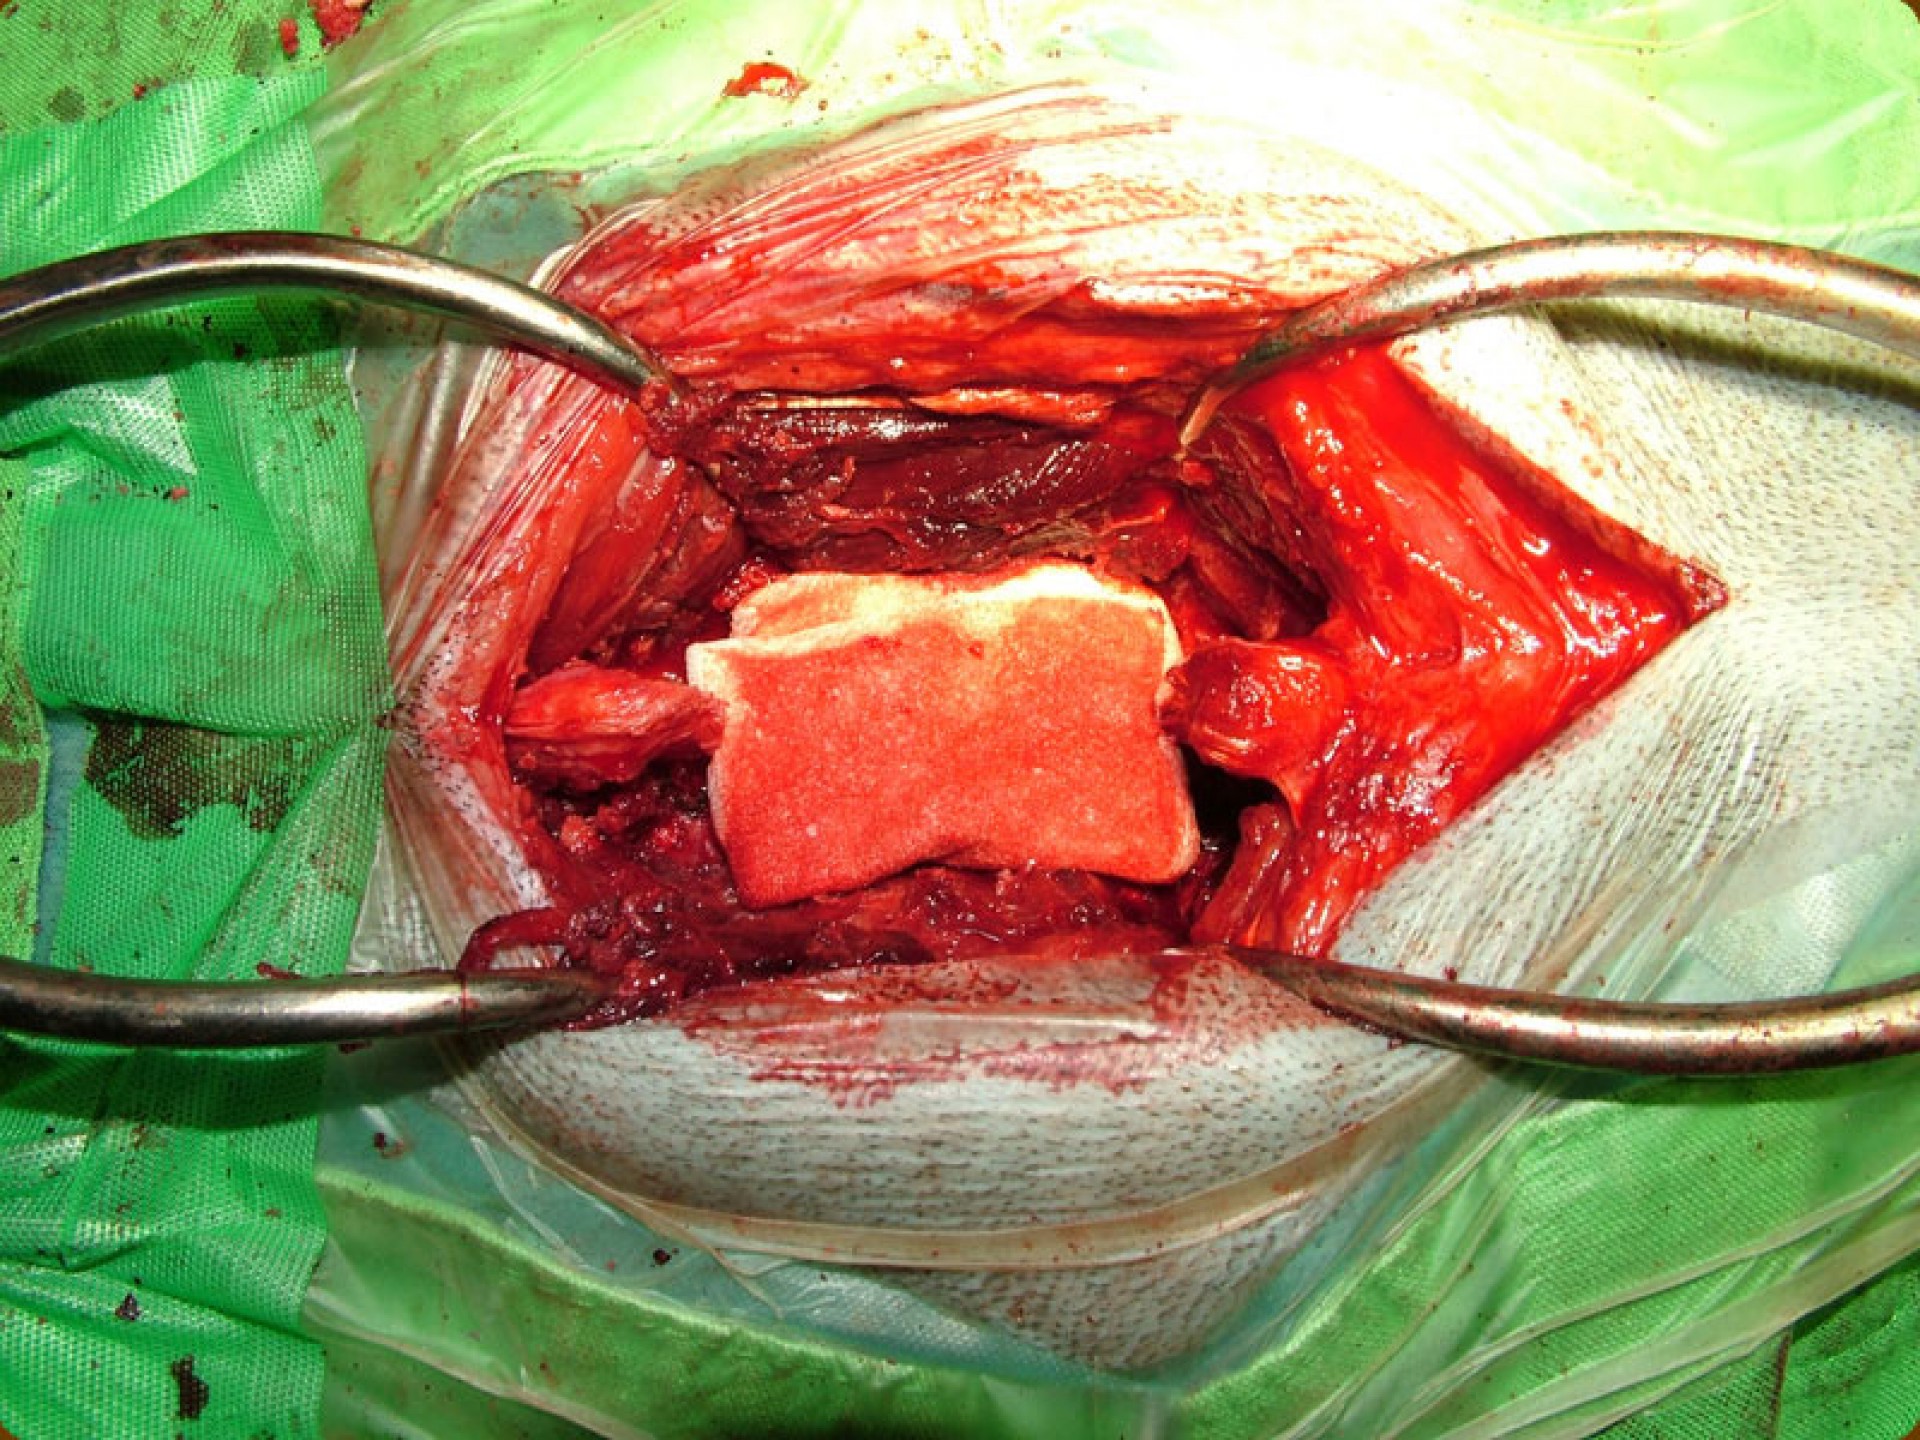

A klinikai tüneteket mutató egyedek korrekt gyógykezelése a bakteriális gyulladás okozta C.E.C. (L7-S1 discospondylitis) kivételével kizárólag műtéti úton lehetséges.A műtét során az összenyomatás helyén a gerincoszlop felső ívének teljes eltávolításával (total laminectomia) lehetőséget biztosítunk a gerincvelőnek arra, hogy a gerincoszlop alsó része felől kialakuló térszűkítő folyamat elől kitérjen.Így megszűnik a gerincvelő összenyomatása, a klinikai tünetek pedig az időben elvégzett műtét esetén jelentősen enyhülhetnek.A discospondylitis esetén legalább 6 héten át tartó antibiotikum és non-szteroid gyulladás- csökkentők együttes adásával érhető el javulás.